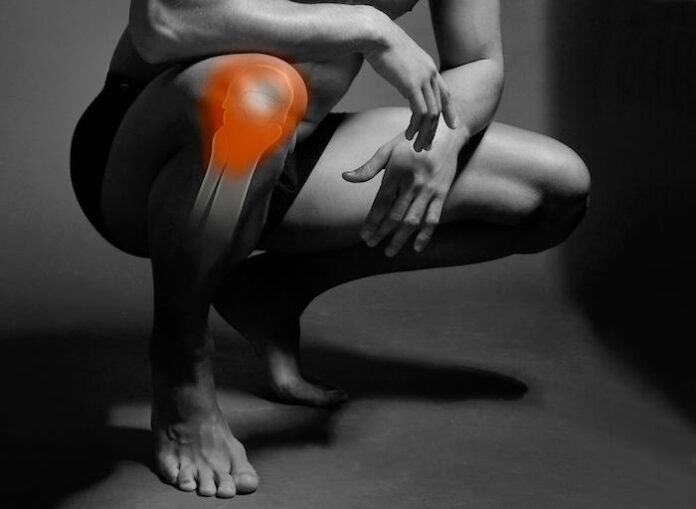

Our knees are probably one of the most crucial joints in our body and also very complex ones. When we are standing, the knee carries 70% of our body weight and almost our entire weight when we bend them. As such, it is exposed to frequent damages due to its specificity. The ACL is one of the ligaments in our knees which makes the connection between the femur and tibia. It also plays a key role in ensuring the stability of our knees. Therefore, this ligament is particularly significant for controlling movements of our knees. When we are injured, we usually face damage to the anterior cruciate ligaments – and sometimes, even a rupture of these ligaments which is an even more severe injury. This kind of damage usually occurs when we practice sports activities. Still, most of these injuries do not occur in contact with the opponent – but most often when landing on a hard surface. However, this doesn’t happen only in sports but can also happen in cases such as falling, hitting the lower part of your leg, traffic accidents, etc.

This type of knee damage usually happens when playing sports, even though that doesn’t have to be the rule. It will most likely happen when we make sudden moves in changing directions. These injuries can often happen when practicing volleyball, basketball, gymnastics, or martial arts. The issue itself is caused by the rotation of the upper and lower parts of the leg in opposite directions and yet, the full weight of the body rests on the leg. It mostly happens in the form of stretching, as a partial or total rupture. Symptoms are pain, knee-swell, bleeding inside the capsule, joint instability, reduced mobility, etc.